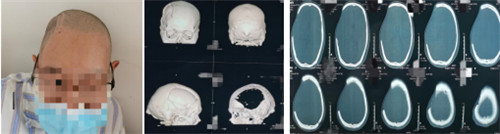

图1.术前外貌,术前颅骨CT平扫及颅骨CT三维成像